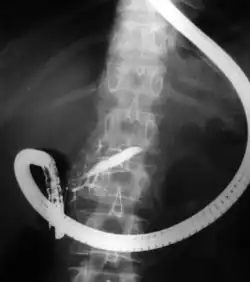

Endoscopic retrograde cholangiopancreatography (ERCP) is a technique that combines the use of endoscopy and fluoroscopy to diagnose and treat certain problems of the biliary or pancreatic ductal systems. It is primarily performed by highly skilled and specialty trained gastroenterologists. Through the endoscope, the physician can see the inside of the stomach and duodenum, and inject a contrast medium into the ducts in the biliary tree and/or pancreas so they can be seen on radiographs.

The patient is sedated or anaesthetized. Then a flexible camera (endoscope) is inserted through the mouth, down the esophagus, into the stomach, through the pylorus into the duodenum where the ampulla of Vater (the union of the common bile duct and pancreatic duct) exists. The sphincter of Oddi is a muscular valve that controls the opening to the ampulla. The region can be directly visualized with the endoscopic camera while various procedures are performed. A plastic catheter or cannula is inserted through the ampulla, and radiocontrast is injected into the bile ducts and/or pancreatic duct. Fluoroscopy is used to look for blockages, or other lesions such as stones.[8][9]

When needed, the sphincters of the ampulla and bile ducts can be enlarged by a cut (sphincterotomy) with an electrified wire called a sphincterotome for access into either so that gallstones may be removed or other therapy performed.[10]

Other procedures associated with ERCP include the trawling of the common bile duct with a basket or balloon to remove gallstones and the insertion of a plastic stent to assist the drainage of bile.[11] Also, the pancreatic duct can be cannulated and stents be inserted.

In specific cases, other specialized or ancillary endoscopes may be used for ERCP. These include mother-baby and SpyGlass cholangioscopes (to help in diagnosis by directly visualizing the duct as opposed to only obtaining X-ray images[13][14][15]) as well as balloon enteroscopes (e.g. in patients that have previously undergone digestive system surgery with post-Whipple or Roux-en-Y surgical anatomy).[16]